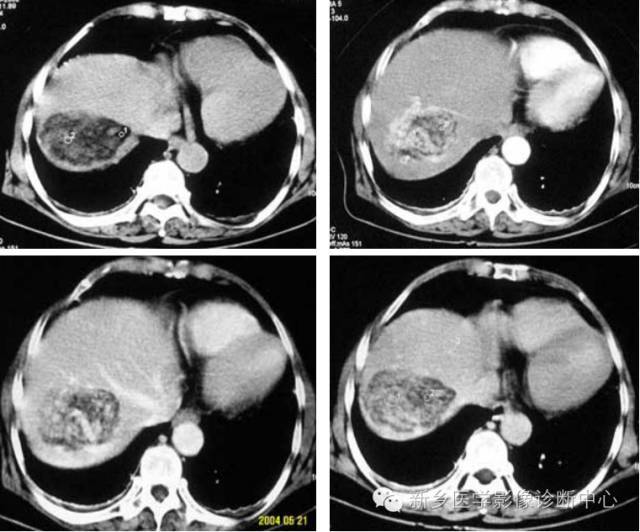

3、肝血管瘤

肝血管瘤在组织学上分为海绵状血管瘤、硬化性血管瘤、血管内皮细胞瘤和毛细血管瘤。是肝脏最常见的良性肿瘤。肝脏的血管瘤多数为海绵状血管瘤。多无临床症状。

病理表现:单发或多发,可位于肝包膜下,向外突出于肝表面,也可比较深在。肿瘤被覆结缔组织被膜,与周围肝组织分界清楚,由充满血液的血管囊腔构成,囊腔间有纤维性分隔。肿瘤可发生纤维化,钙化及血栓形成。

CT表现特点:病灶多为圆形或类圆形,边界清楚但无假包膜。平扫呈均匀低密度,增强扫描病灶边缘呈明显的不连续的结节状强化,强化区域进行性向中心扩展。延迟扫描病灶呈高密度充填。较大的病灶中心可见始终不充填。

血管瘤与其他富血供肿瘤的鉴别:①血管瘤的强化与血管相当。②血管瘤在延迟影像上呈持续强化。③血管瘤有周围结节样强化,其环内缘呈波浪状,而肝转移瘤其强化环内缘凹凸不平。④血管瘤增强后呈进行性持续性、向心性强化,无“周围洗脱”现象。